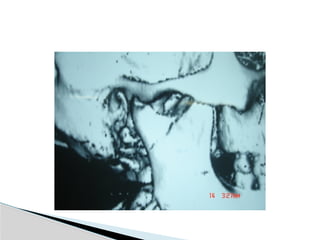

Conventional Radiology

At least 2 views at right angle to each other.

Mandibular series: PA, Lateral oblique or

panoramic, & Towne’s view (projects condyle

below mastoid process).

CT

Significant displacement or dislocation,

mechanical obstruction, mult trauma pt, &

intracapsular fracture.

MRI

St injuries: effusion, visualization of disc.

Imaging